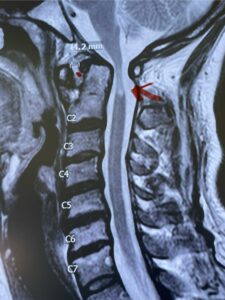

Fig. 4a: Sagittal T2-weighted cervical MRI demonstrating severe cord compression with myelomalacia of upper cervical spinal cord (red arrow). Notice the increased atlanto-dens interval (red dot).

Fig. 6a: Sagittal cervical CT scan demonstrating an abnormally thin right C2 isthmus prohibiting safe placement of screw (red arrow). Notice the vertebral foramen eroding the isthmus bone structure (red dot).